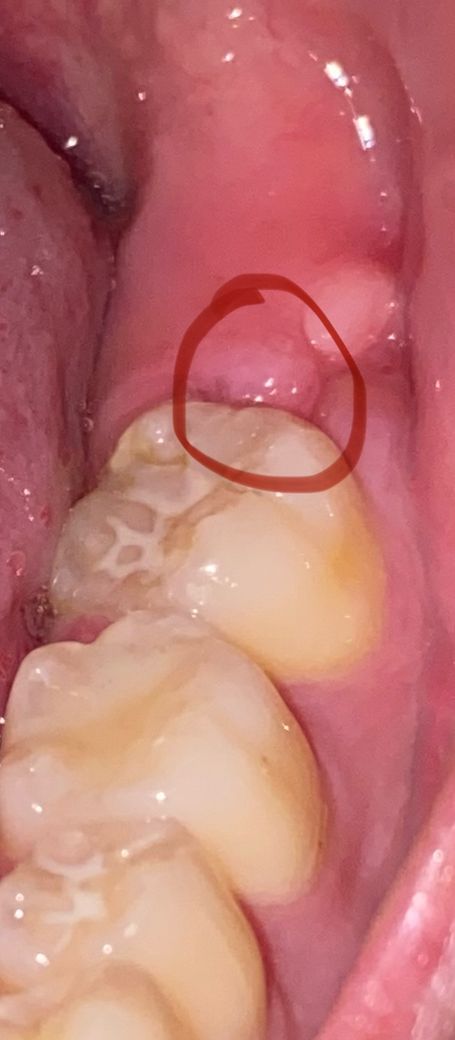

38번 사랑니 뽑은지 6달정도 지나고 현재는 잇몸이 거의 아물었는데 사진에서 보다시피 며칠전부터 동그라미 친 부위가 욱신 거리면서 아픕니다. 37번 원심면 바로 뒤 잇몸이요. 뭐 먹을 때 아프고 칫솔이 닿았을 때도 아프고 침 삼킬 때도 아픕니다. 거울로 보니까 저 부위에 약간 좁쌀같은 엄청 작은 여드름 같은?게 있길래 그거 짰는데 고름 같은건 안나오고 그냥 피가 아주 살짝 나고 말았습니다.

• 1번 째 사진